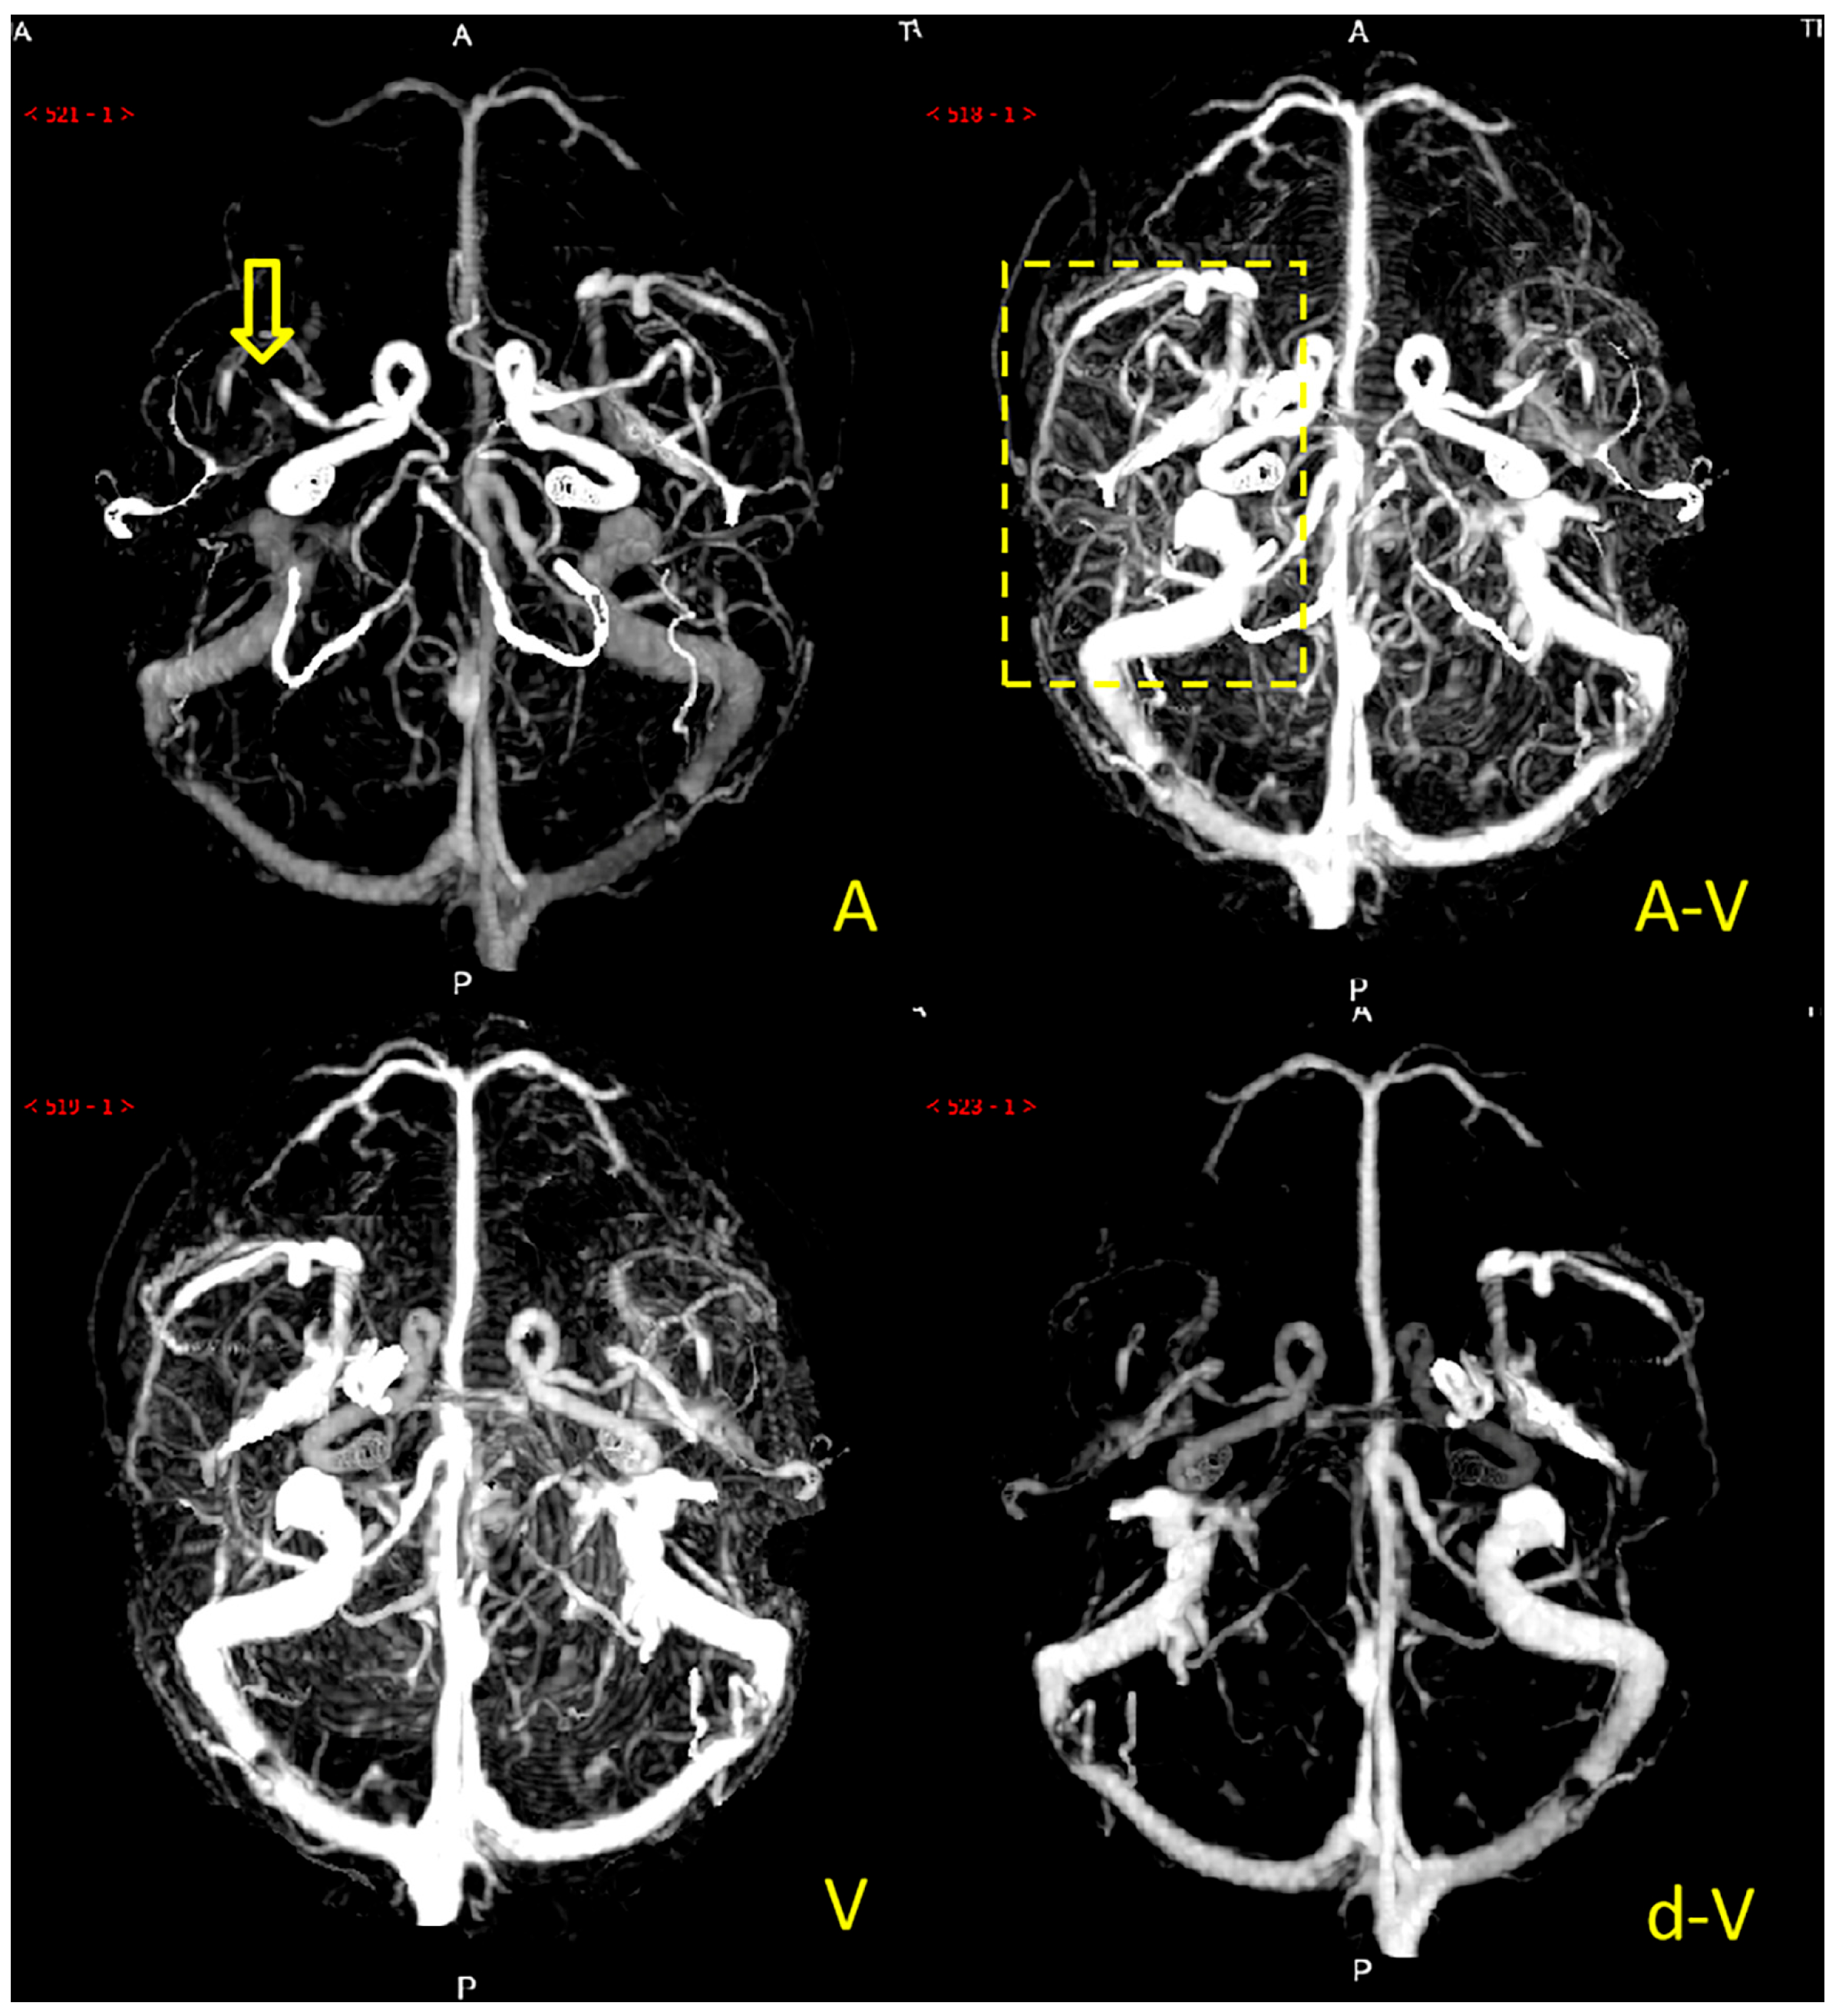

Collateral circulation grading was performed using a modified ASITN/SIR (American Society of Interventional and Therapeutic Neuroradiology/Society of Interventional Radiology) collateral grading scale based on dynamic multi-period CTA [5,14,15]. The scale consists of 5 levels: level 0 indicates no or few collateral branches in the ischemic area at any stage; level 1 is partial collateral circulation until the late venous phase; level 2 is partial collateral circulation in the ischemic area before the venous phase; level 3 is complete collateral circulation formation in the ischemic area in the late venous phase, and level 4 is total collateral circulation before the venous phase. Grades 0 to 2 were defined as poor collateral circulation (Figure 2), while grades 3 to 4 were defined as good collateral circulation (Figure 3). We marked patients as having good or poor collateral circulation according to each patient’s dynamic CTA collateral grading. Two experienced neuroradiologists performed the scoring, and they negotiated a solution if they had a different opinion. The scoring process was blinded to the clinical data.

Figure 2. Example of a patient with poor collateral circulation. Note: The patient’s left middle cerebral artery was occluded (the yellow arrow), and there was no major collateral vessel in the left middle cerebral artery blood supply area (the yellow dashed box) of A (arterial phase), A-V (arteriovenous phase), V (venous phase), and d-V (venous late phase).